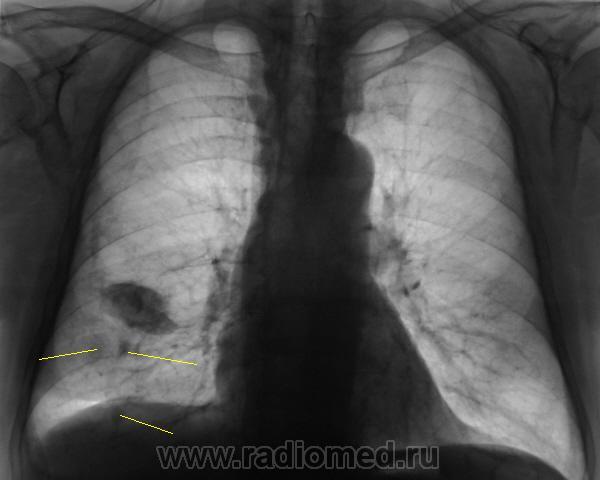

Флюорограмму расшифровывал врач того учреждения, откуда флюорограф, ну и рекомендацию "что сделать" - от туда. Но с учетом наличия синдрома "затемнения вне анатомических границ", конечно, лаборанты сделали и боковую, а уже только после этого пригласили "нашего" врача-рентгенолога "для принятия решения".

И фрагмент с увеличением. Что посоветуете tatyana ?

Конечно, я понимаю, что должна быть проведена д/д между "осумковнным выпотом" и "швартообразующим процессом". Что посоветуете?

Повезло с лаборантами!.. Поскольку, помимо междолевого ограниченого плеврита, мне мерещатся еще очаги в легком, посоветую КТ

Я пока, это никак не трактую. Случай сегодняшний, думаю. Может коллеги, чего подскажут. Вот и последний срез. Подумываю, что в наличии и "базальный" выпот.